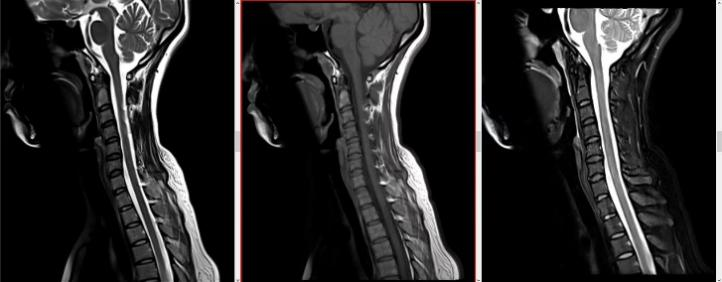

我们的服务项目涵盖了全身各部位的影像检查,包括但不限于:头部、颈部、胸部、腹部、盆腔、四肢等部位的CT、MRI、DR等检查。我们还提供特殊的影像检查服务,如血管造影、MR多功能成像等。例如:

磁共振检查: